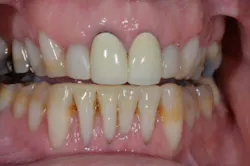

Once the patient is completely comfortable and happy with the provisionals, we take a new set of photos, facebow, bite registration, and models to communicate with the ceramist, who will complete the fourth version of the case—in porcelain.

With proper planning and forethought, even the most complex cases can be broken down into a series of simple steps. It all starts with a complete exam and diagnosis, followed by a properly developed plan that meets the patient’s goals and the requirements for a stable occlusion.

Once we have a finished wax-up of our treatment objectives, we can make a series of putty matrices and reduction guides to be used in a thoughtful, sequential manner to transfer our plan to the mouth. By taking a programmed approach, it is possible to eliminate guesswork and introduce predictability in even the most complex of cases.